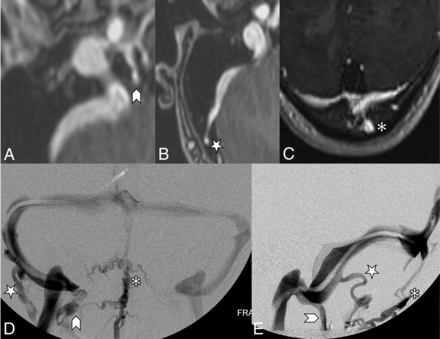

The other recorded imaging findings included the presence or absence of prominent emissary veins, optic nerve tortuosity, cephalocele, sella appearance, sinus enlargement versus aneurysm, and internal jugular bulb diverticula as shown in Fig 3. The presence of prominent emissary veins was initially detected on MRV and corroborated on subsequent conventional venography. The 3 subtypes classified were condylar arising from the internal jugular bulb, mastoid arising from the sigmoid sinus, and occipital arising from the torcula as shown in Fig 4.

Contrast-enhanced MRV images (A, B, and C) highlighting features of the emissary veins categorized in this study. A, A condylar vein is seen arising from the internal jugular vein bulb extending through the condylar canal (arrowhead). B, A mastoid emissary vein is seen arising from the sigmoid sinus traversing the mastoid foramen (star). C, An occipital emissary vein is seen arising from the torcula extending through the calvaria (asterisk). Conventional venography frontal (D) and lateral (E) images showcase the 3 emissary vein types categorized in this study. The condylar vein (arrowhead) extends inferiorly toward the vertebral plexus. The mastoid emissary vein (star) extends posteriorly and inferiorly to join the suboccipital plexus and external jugular vein. The occipital emissary vein (asterisk) drains inferiorly into the suboccipital plexus.